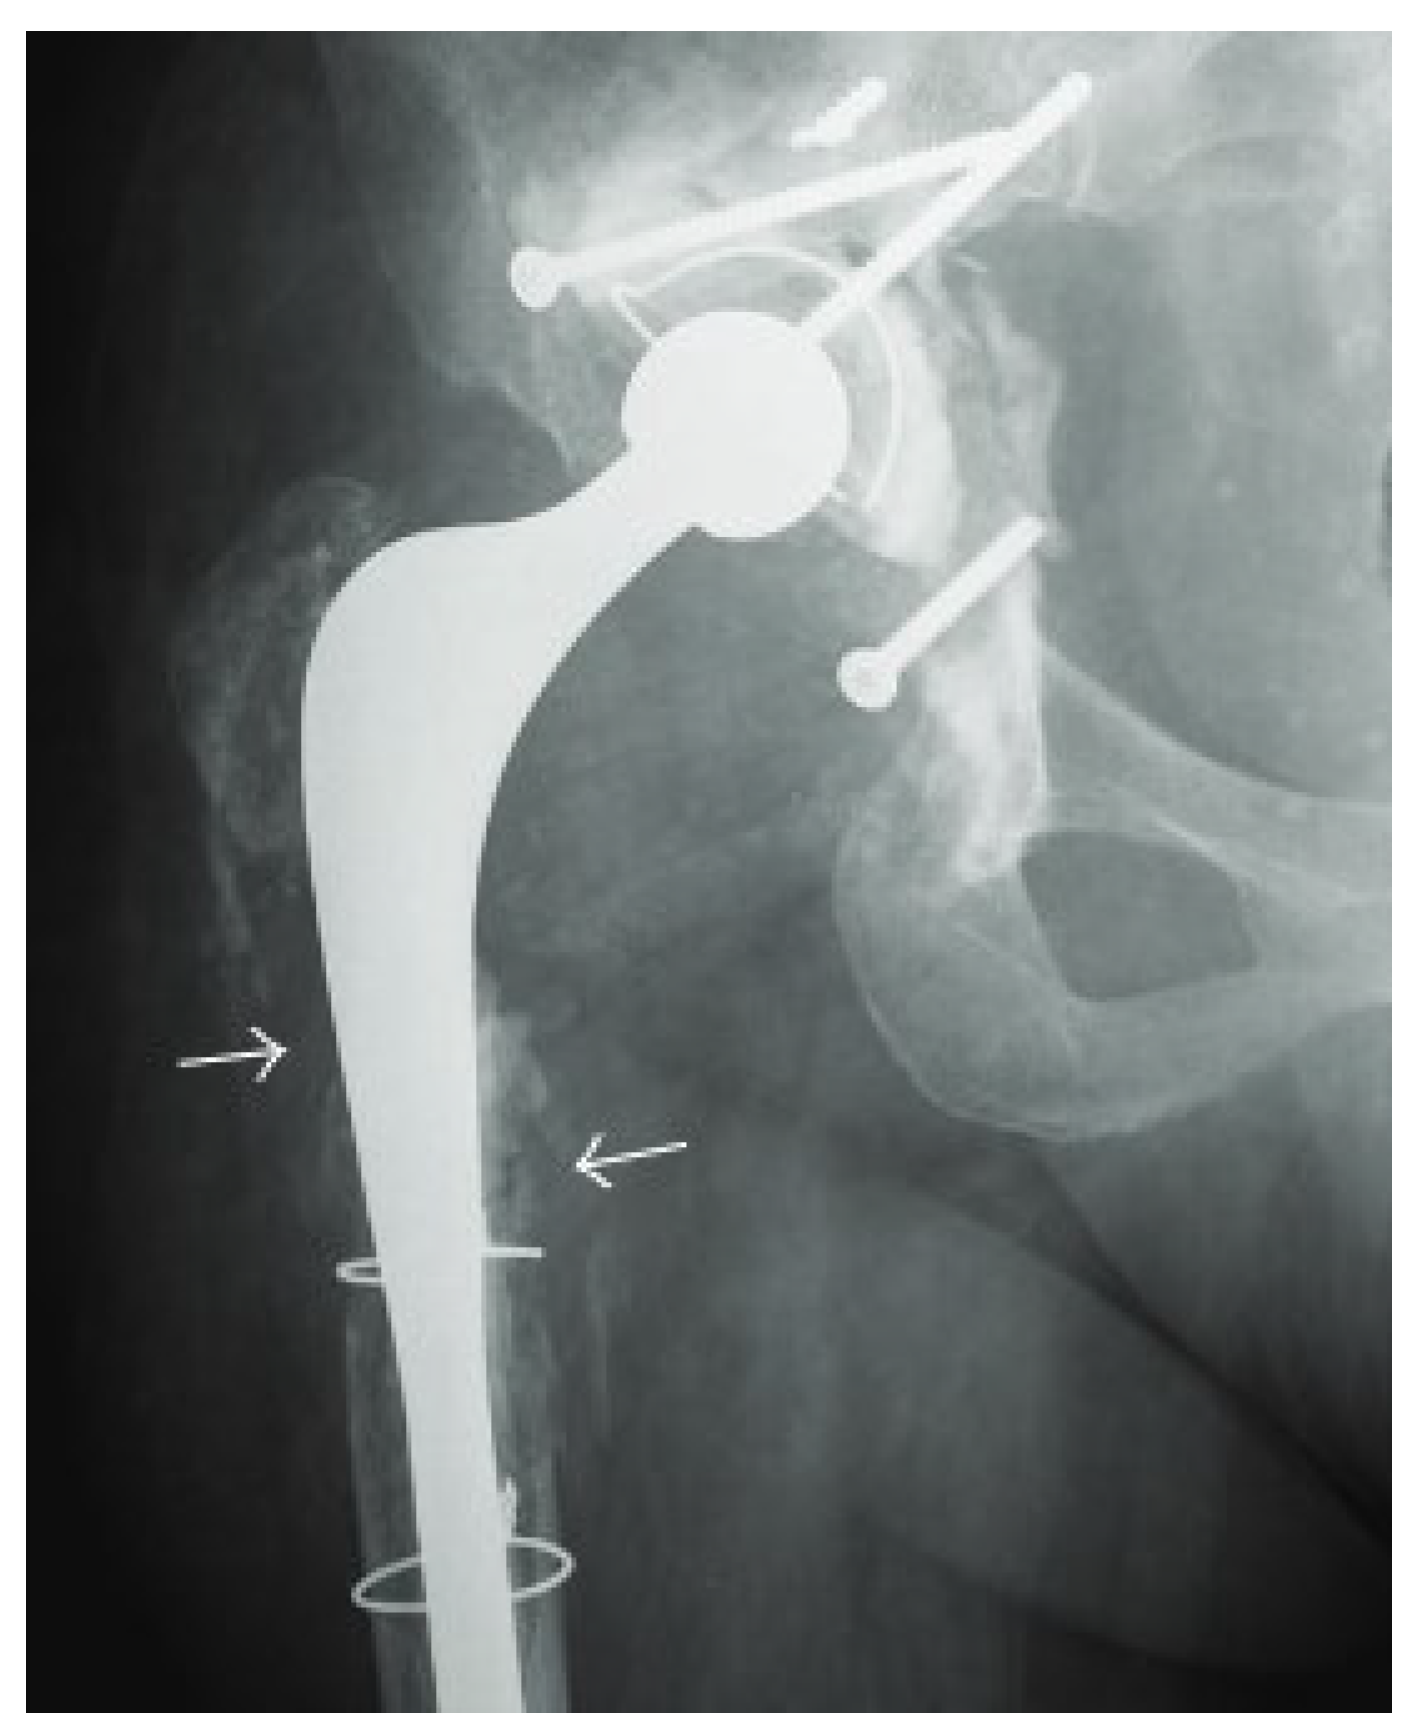

4.1. Radiography

- Hofmann, U.K.; Eleftherakis, G.; Migliorini, F.; Fink, B.; Mederake, M. Diagnostic and prognostic relevance of plain radiographs for periprosthetic joint infections of the hip: A literature review. Eur. J. Med. Res. 2024, 29, 314. [Google Scholar] [CrossRef]

- Li, N.; Kagan, R.; Hanrahan, C.J.; Hansford, B.G. Radiographic evidence of soft-tissue gas 14 days after total knee arthroplasty is predictive of early prosthetic joint infection. Am. J. Roentgenol. 2020, 214, 171–176. [Google Scholar] [CrossRef] [PubMed]

- Weissman, B.N.; Palestro, C.J.; Fox, M.G.; Bell, A.M.; Blankenbaker, D.G.; Frick, M.A.; Jawetz, S.T.; Kuo, P.H.; Said, N.; Stensby, J.D.; et al. ACR Appropriateness Criteria® Imaging After Total Hip Arthroplasty. J. Am. Coll. Radiol. 2023, 20, S413–s432. [Google Scholar] [CrossRef] [PubMed]